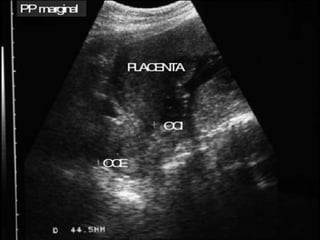

PLACENTA PREVIA

Es la implantación y desarrollo de la placenta en

el segmento inferior del útero, donde la placenta

se encuentra cerca o incluso cubriendo el

orificio cervical interno (OCI).

Marginal

Lateral o

inserción

baja de

placenta

Oclusiva

parcial

total

• Historia clínica

• Ultrasonografia

pélvica: el

diagnóstico

contundente se

hace a través de

este examen (95 a

98%).

Diagnostico